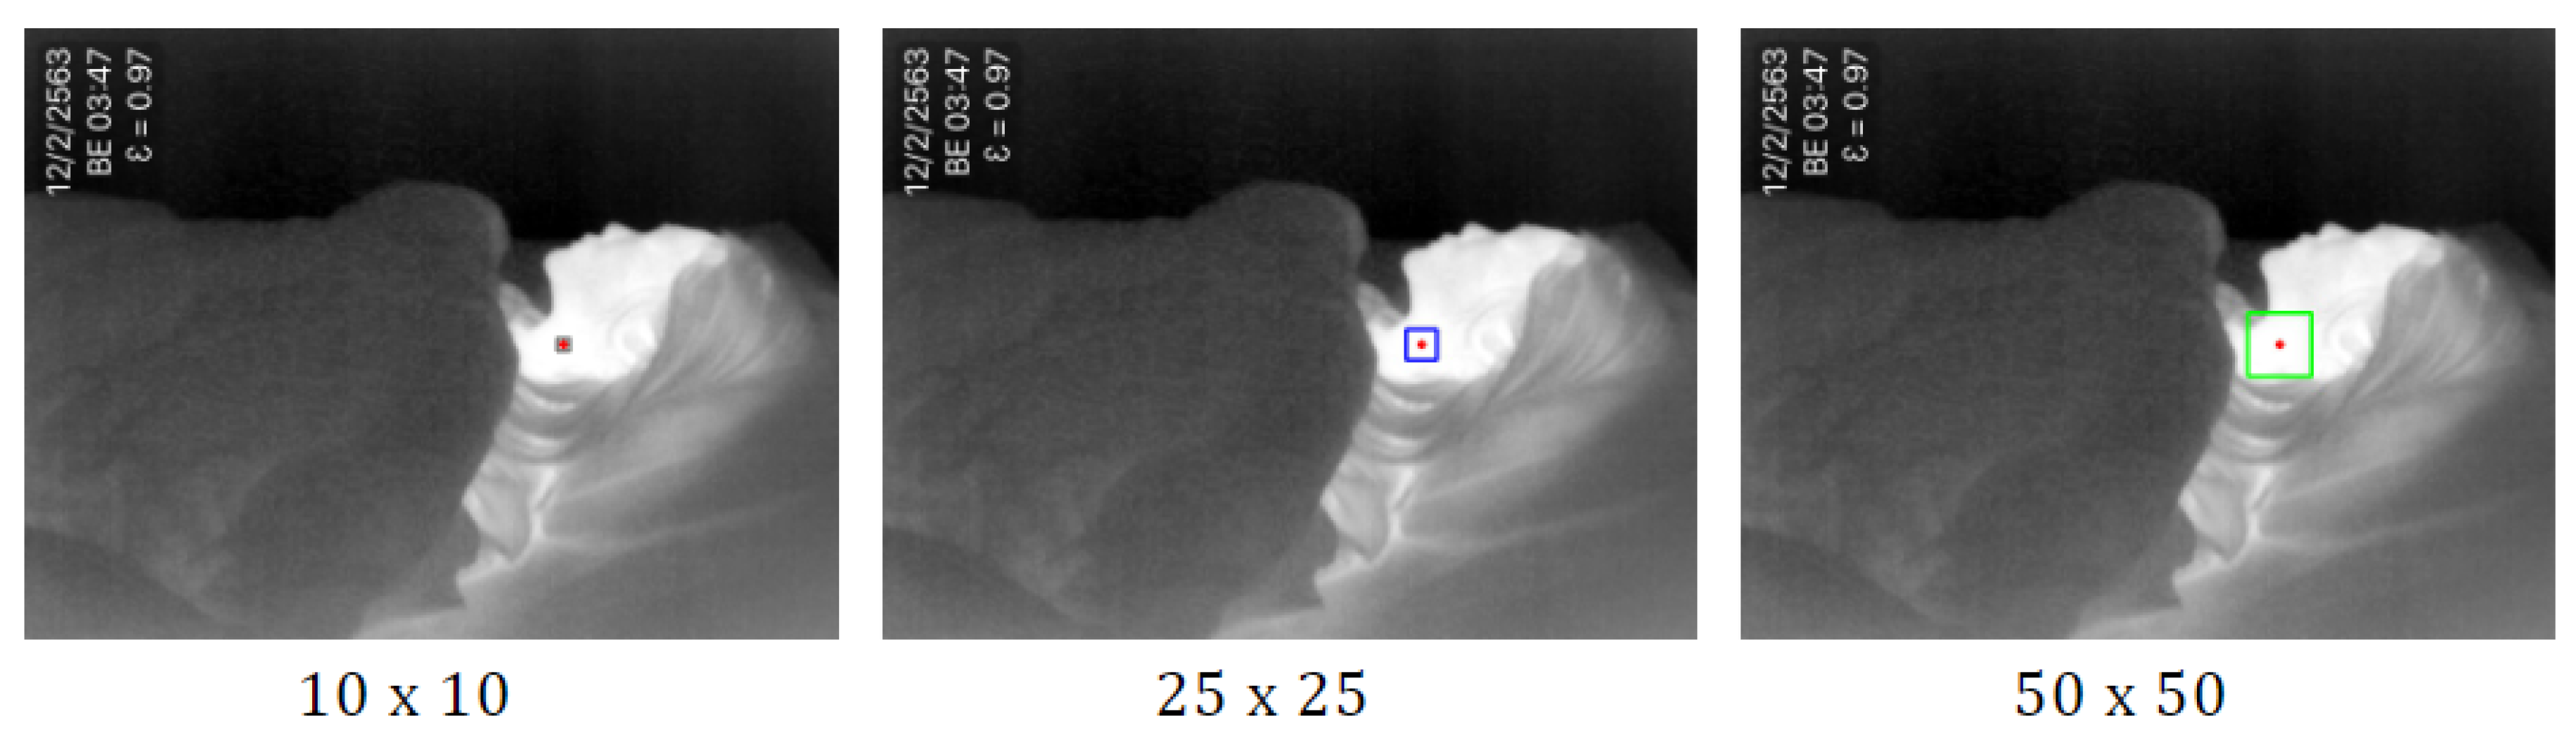

- The highest temperature point is detected by using minMaxLoc. The minMaxLoc function is one of the OpenCV [38] libraries that returns minimum and maximum intensities found in an image with their (x,y) coordinates. It is assumed that the maximum pixel intensities of the thermal image refer to a human’s heat signature that is not covered by a blanket. The maximum pixel intensities found in the image correspond to the highest temperature of the body. We set the pixel to the center of the observation area. Then we draw a rectangle around the pixel, with the size of the square pixels depending on original frame resolution. In [39], the authors compared the ROI size of , , , , and pixels. They found that the size of the ROIs for respiratory rate estimation is usually smaller than that for heart rate estimation. Therefore, in this study, we consider the three different sizes as , , and , as shown in Figure 2. The result in empirical research has shown that the pixels provided the highest accuracy in accordance with the original frame resolution of 640 × 480.

Figure 2. The sample of three different sizes as , , and (red point indicates the highest temperature point). - (2)